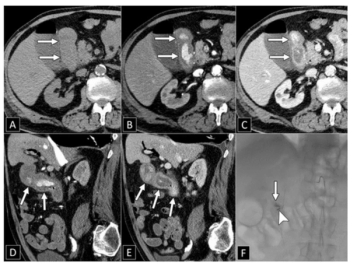

In joint consensus recommendations issued from the Society of Abdominal Radiology and the American College of Gastroenterology, researchers discussed key pearls, benefits, and limitations of CT angiography for imaging of overt lower GI bleeding and CT enterography for detecting small bowel bleeding.